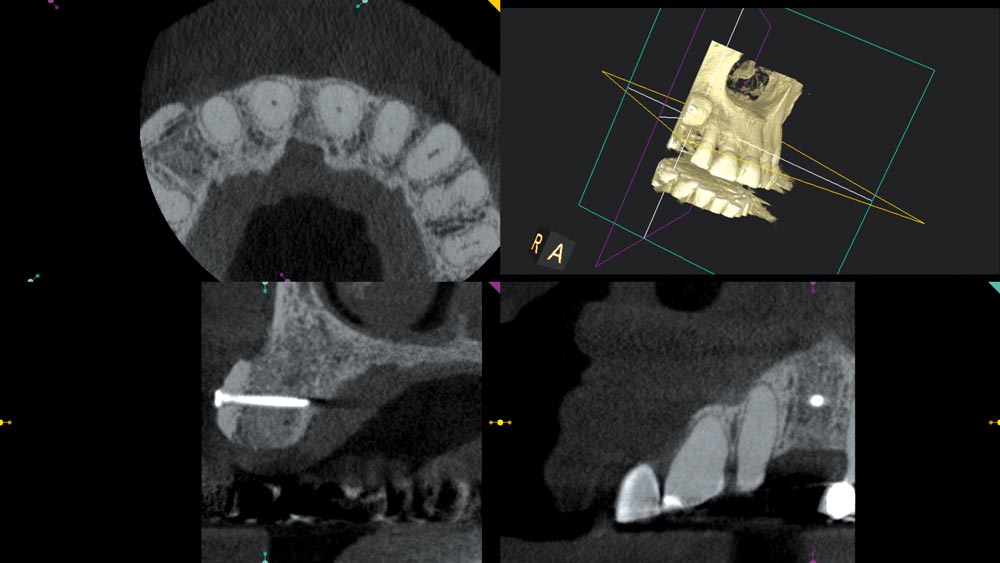

03/12 - Initial CBCT scan

Block augmentation with maxgraft® in the maxilla - PD Dr. Dr. F. Kloss